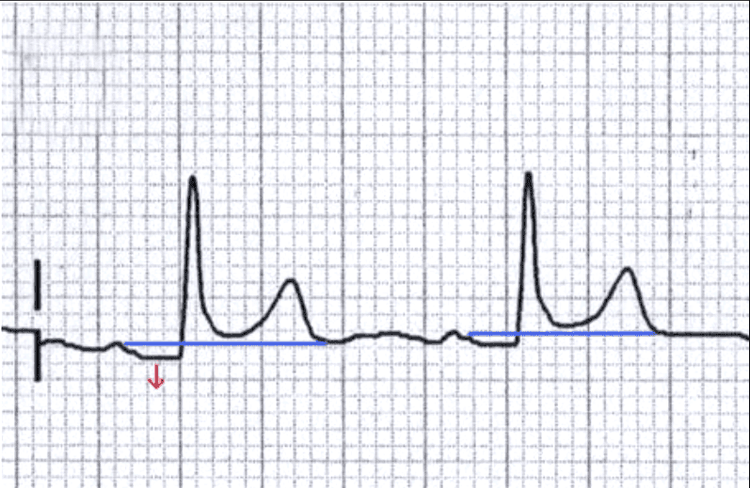

3.6. Đoạn ST

- ST bình thường là đẳng điện

- Thay đổi liên quan đến tổn thương mới cơ tim hoặc viêm màng ngoài tim; phì đại thất; thuốc digoxin

- Có thể chênh lên; chênh xuống...

- Các hình dạng khác nhau, các vị trí khác nhau cho phép chẩn đoán bệnh.